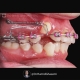

درمان ارتودنسی بدون جراحی و بدون کشیدن دندان در کیس کلاس ۲ دیپ بایت.

Non surgical and non extraction orthodontic treatment of class 2 deepbite case.